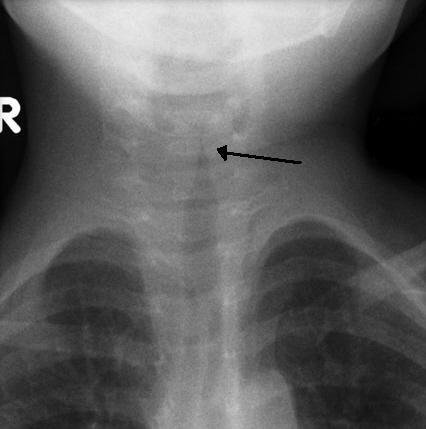

CXR - different diagnosis, croup may show a steeple sign where the trachea is seen to taper.